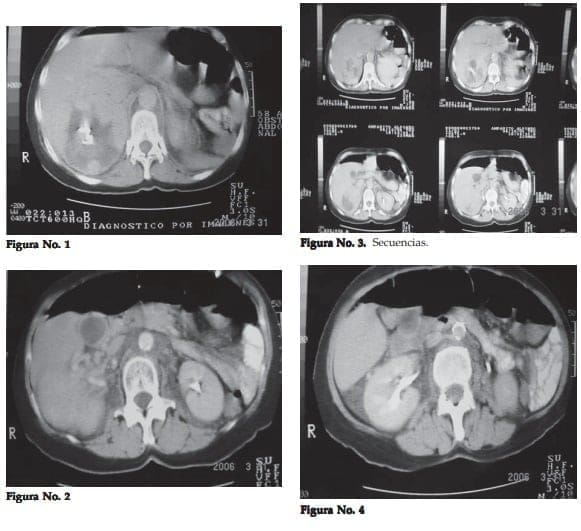

Finalmente un TAC abdominal informa de un tumor maligno (hipernefroma) del polo superior del riñón derecho (figuras 1, 2, 3 y 4).

Se revisó el TAC con el radiólogo llegando a la conclusión de que sí podría tratarse de un tumor suprarrenal, maligno por su mayor tamaño, desplazamiento renal, no deformación calicial superior y en una secuencia se observa con mayor nitidez la masa tumoral.